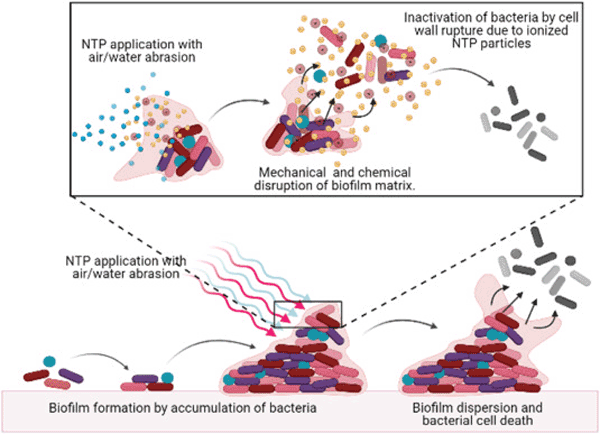

Poor Oral Hygiene

Neglecting regular brushing, flossing, and dental check-ups leads to plaque and tartar buildup on teeth and gums. This plaque, combined with dietary sugars, fosters bacterial growth, resulting in gum inflammation (gingivitis) and tooth decay.